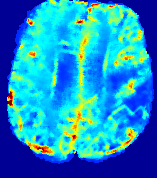

LesionRefer to captionRefer to captionRefer to captionRefer to captionRefer to captionRefer to caption𝐕rgbsubscript𝐕𝑟𝑔𝑏{\bf{V}}_{rgb}Refer to captionRefer to captionRefer to captionRefer to captionRefer to captionRefer to caption𝐕2subscriptnorm𝐕2{\|\bf{V}}\|_{2}Refer to captionRefer to captionRefer to captionRefer to captionRefer to captionRefer to captionRefer to caption3.53.53.52.82.82.82.12.12.11.41.41.40.70.70.70.00.00.0(mm/s)𝑚𝑚𝑠(mm/s)D𝐷DRefer to captionRefer to captionRefer to captionRefer to captionRefer to captionRefer to captionRefer to caption0.0200.0200.0200.0160.0160.0160.0120.0120.0120.0080.0080.0080.0040.0040.0040.0000.0000.000(mm2/s)𝑚superscript𝑚2𝑠(mm^{2}/s)Slice #1Slice #2Slice #3Slice #4Slice #5Slice #6

Figure 3: PIANO feature maps for one stroke patient, where the lesion is located in the left hemisphere. Top row: segmented stroke lesion region (white) on different slices, obtained from ISLES 2017. The corresponding slices for the PIANO feature maps are shown in the following rows.

For a better insight into an estimated velocity field 𝐕𝐕{\bf{V}} and diffusion field 𝐃𝐃{\bf{D}}, we compute the following maps: (1) 𝐕rgbsubscript𝐕𝑟𝑔𝑏{\bf{V}}_{rgb}: Color-coded orientation map of 𝐕=(Vx,Vy,Vz)T𝐕superscriptsuperscript𝑉𝑥superscript𝑉𝑦superscript𝑉𝑧𝑇{\bf{V}}=(V^{x},V^{y},V^{z})^{T}, obtained by normalizing 𝐕𝐕{\bf{V}} to unit length and mapping its 3 components to red, green, blue respectively; (2) 𝐕2subscriptnorm𝐕2\|{\bf{V}}\|_{2}: 222 norm of 𝐕𝐕{\bf{V}}; (3) D𝐷D: scalar field in Eq. 5.

Fig. 3 and Fig. 4 show the PIANO feature maps estimated from two ISLES 2017 patients: all are highly consistent with the lesion in both cases. Details of the blood flow trajectories are revealed in 𝐕rgbsubscript𝐕𝑟𝑔𝑏{\bf{V}}_{rgb} by the ridged patterns and the sharp changes of colors in the unaffected (right) hemisphere, while the flat patterns appearing within the lesion provide little directional information about the velocity and indicate low velocity magnitudes. Velocity magnitudes are more directly visualized via 𝐕2subscriptnorm𝐕2\|{\bf{V}}\|_{2}, from which one can easily locate the lesion where 𝐕2subscriptnorm𝐕2\|{\bf{V}}\|_{2} is low. D𝐷D also indicates lower diffusion values in the lesion, though with less contrast potentially due to the fact that it captures the accumulated effect of CA diffusion at the voxel-level.